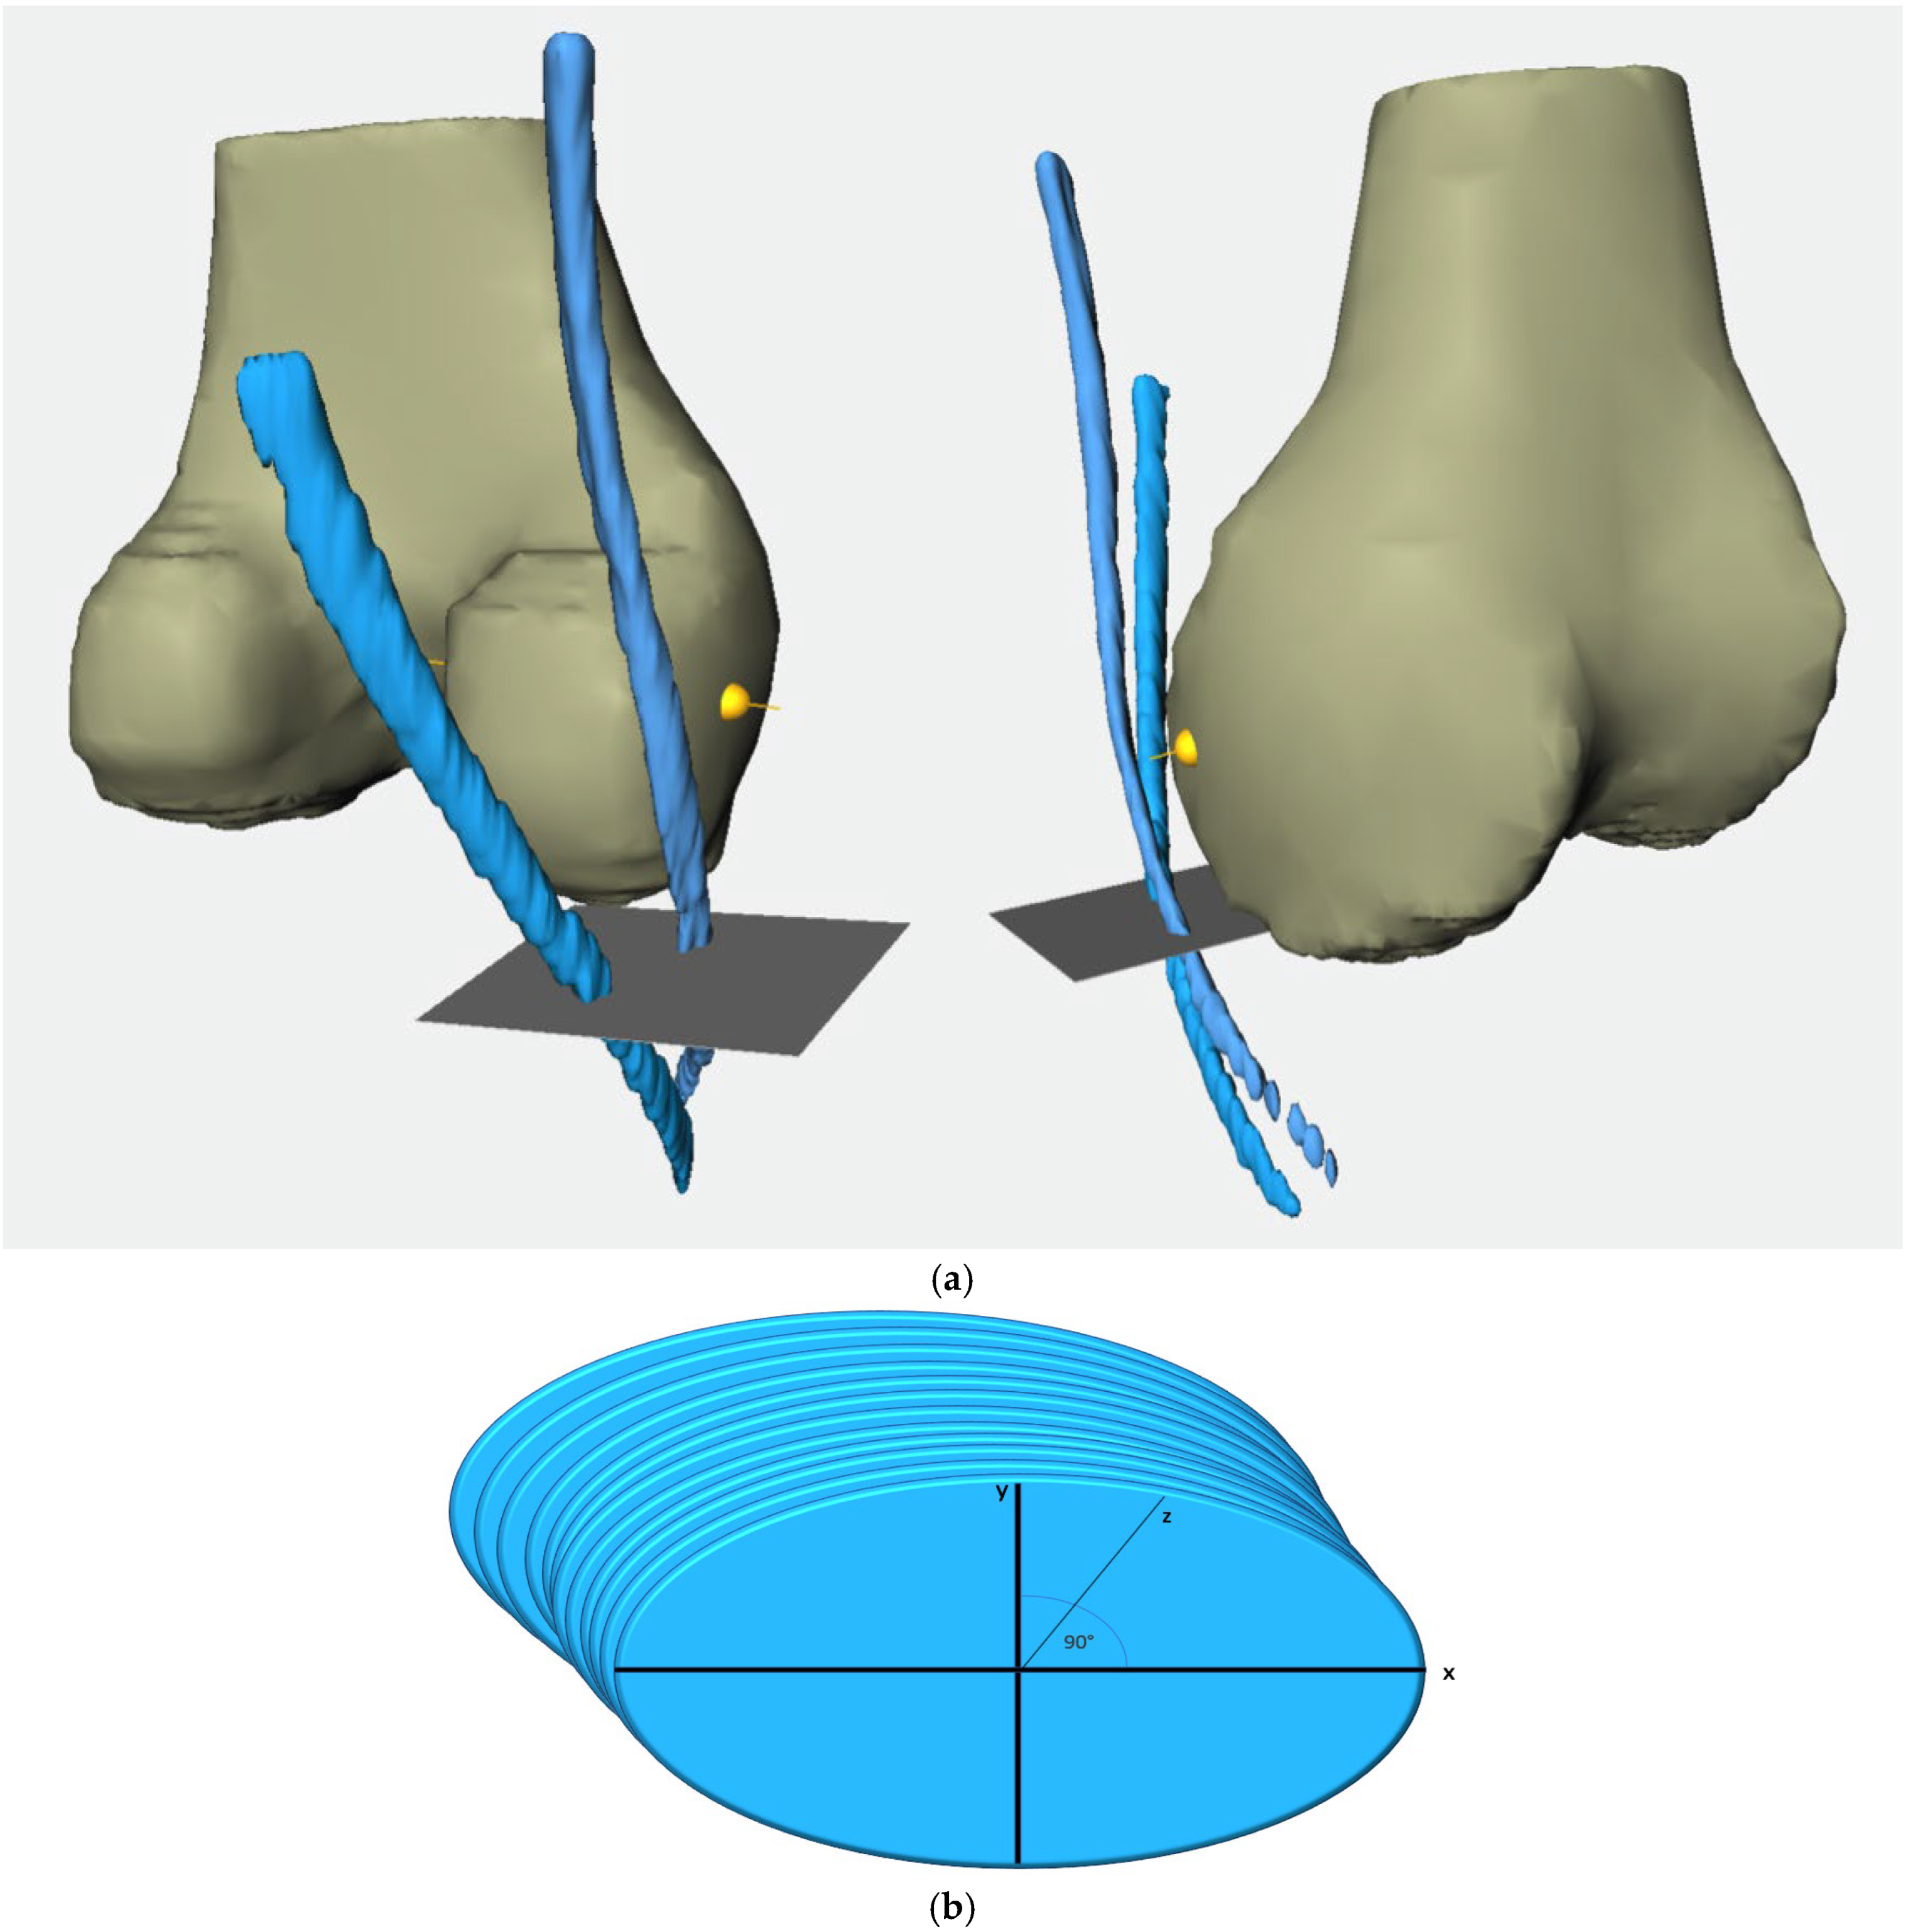

2.2. Methodological Approach

- From 20 mm above the joint line to the joint line (20 mm–0).

- From 10 mm above the joint line to the joint line (10 mm–0).

- From 10 mm below the joint line to 10 mm above the joint line (−10 mm–10 mm).

- From 10 mm below the joint line to the joint line (−10 mm–0).

- From 20 mm below the joint line to the joint line (−20 mm–0).

- From the widest intercondylar diameter to the joint line (0–WID).